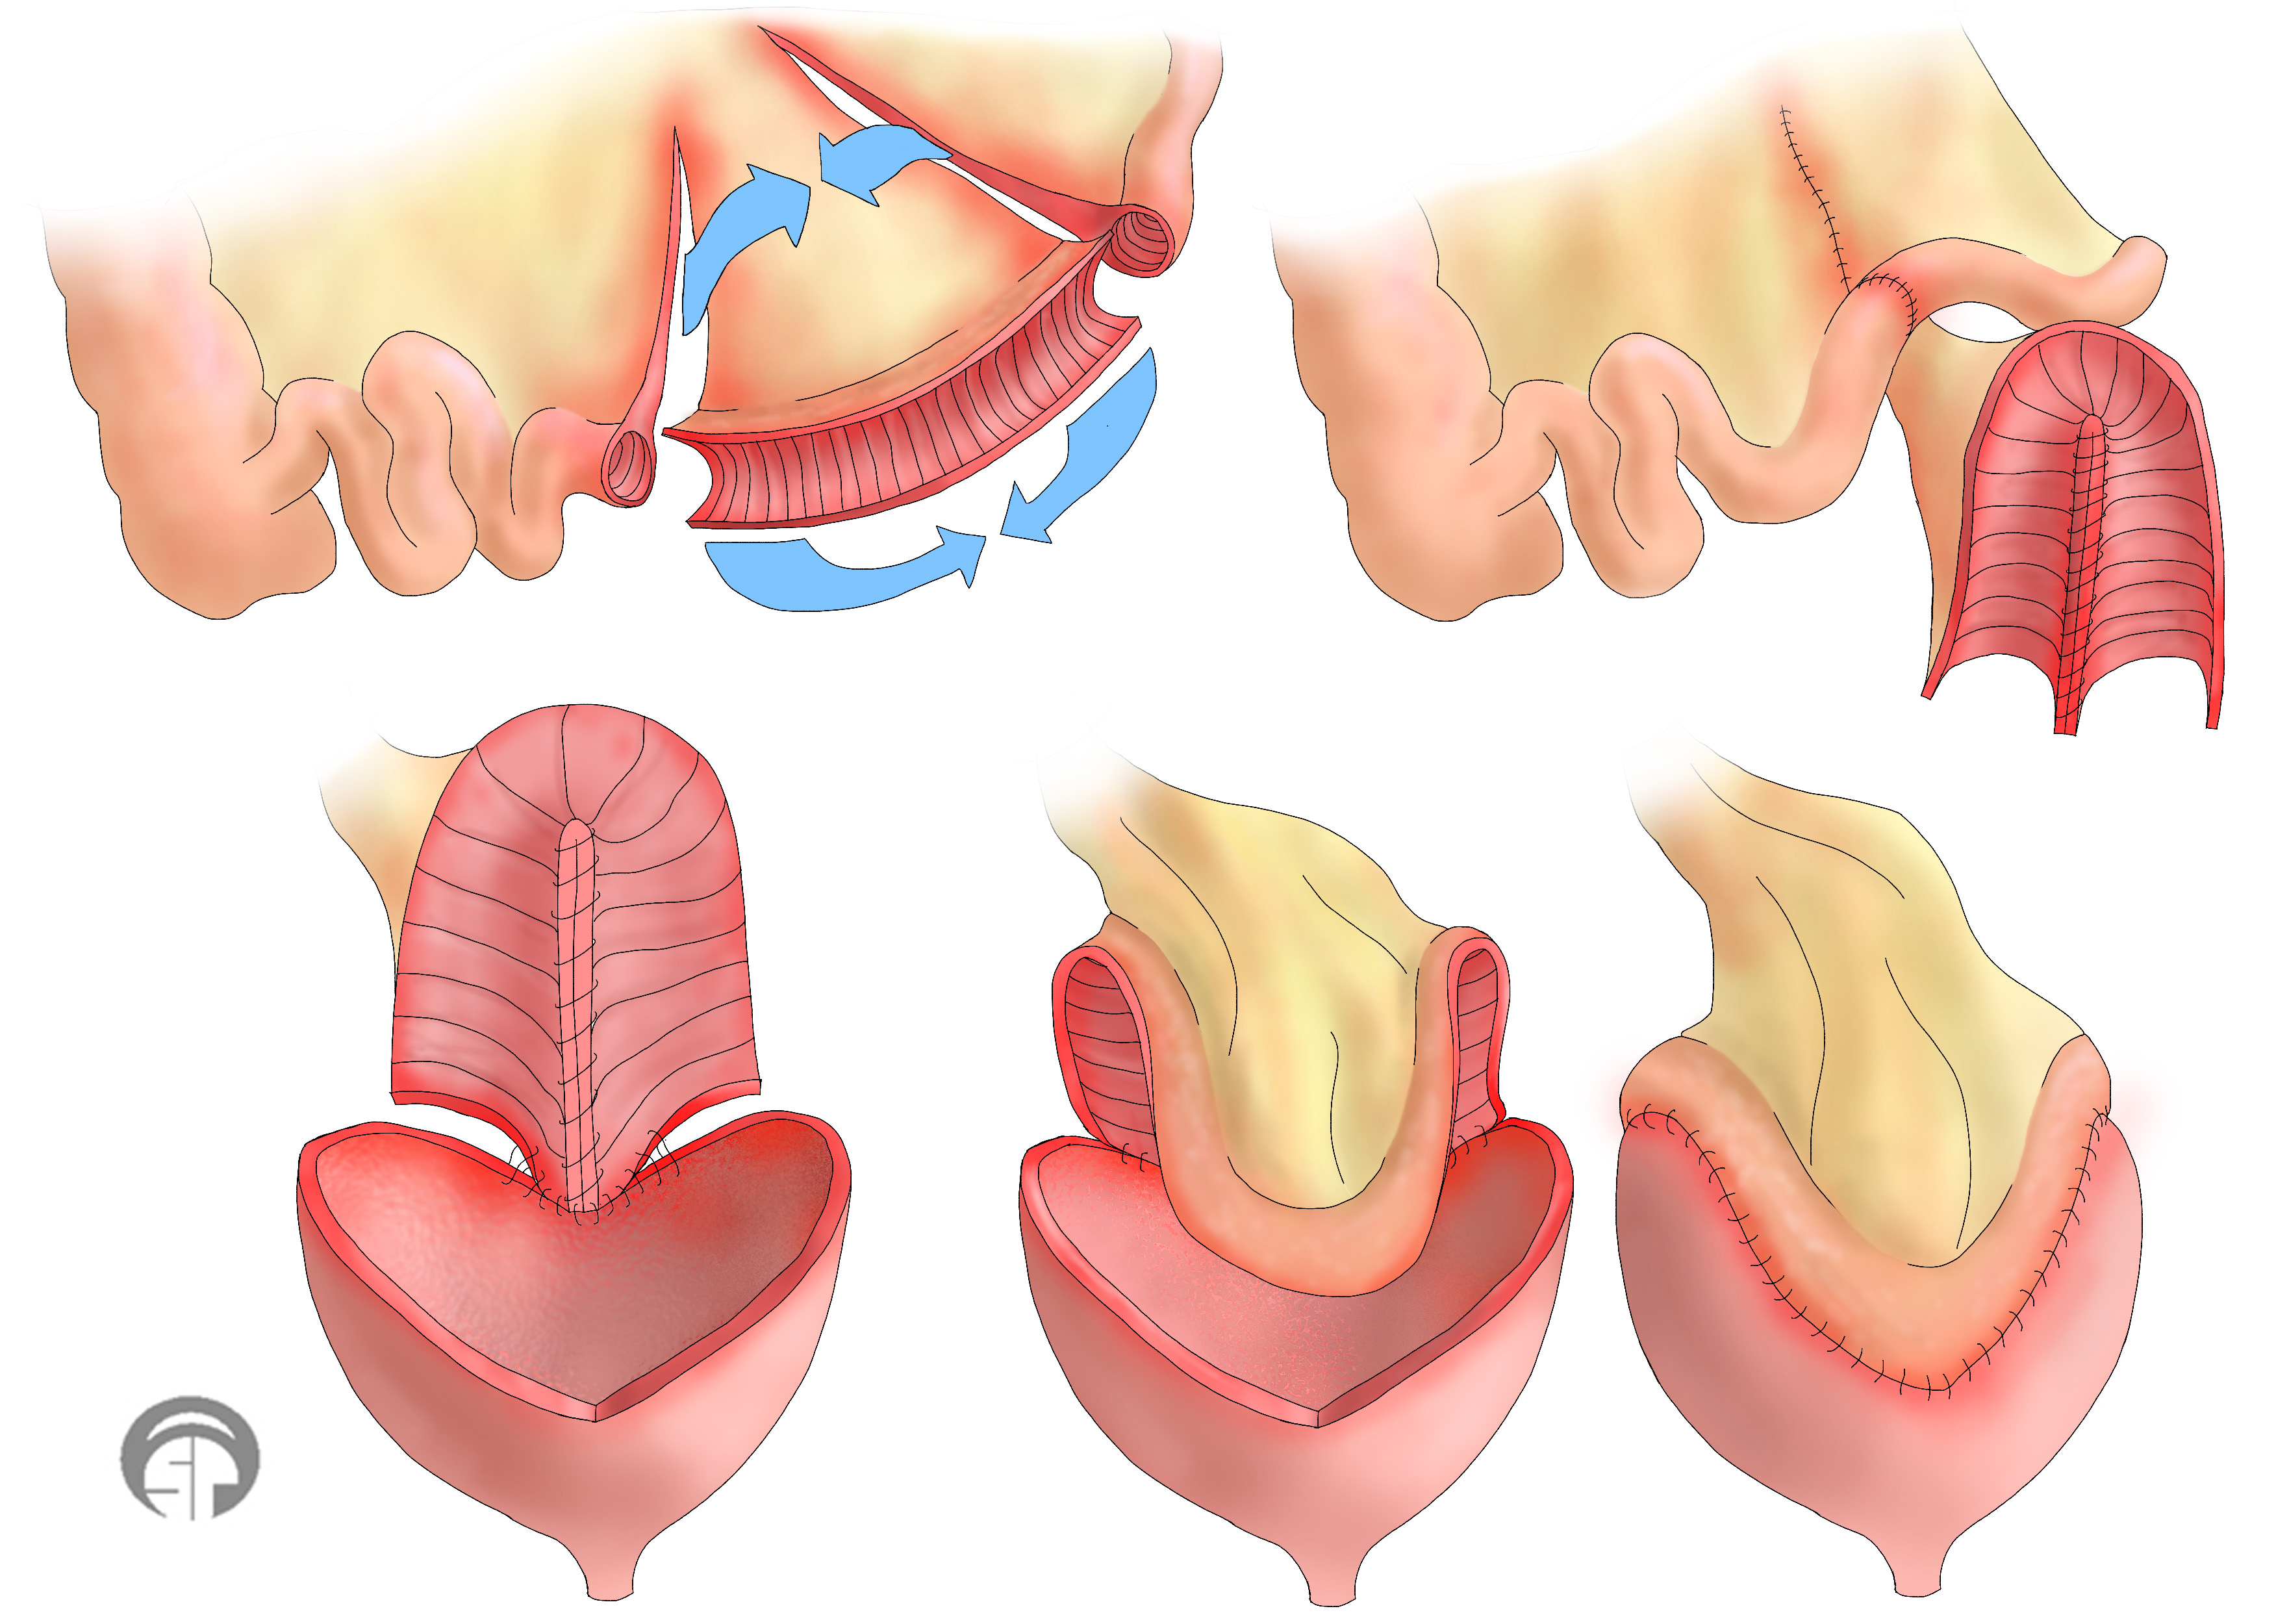

Лабиопластика, также известная как лабиопластика, заключается в хирургической модификации больших или малых половых губ, но чаще всего это уменьшение размера малых половых губ (рис.) и является одной из наиболее часто выполняемых процедур FCGS. Часто цель состоит в том, чтобы сохранить контур губ и сохранить цвет губных краев. Различные хирургические методы включают криволинейную резекцию, резекцию V-образным клином, резекцию нижнего клина и реконструкцию верхнего лоскута на ножке, Z-пластику и другие менее используемые методы.

Вагинопластика предназначена для хирургического сужения влагалищного канала и включает удаление избыточной слизистой оболочки влагалища из сводов влагалища.Он может включать переднюю кольпорафию, заднюю кольпорафию, иссечение латеральной слизистой оболочки влагалища или различные комбинации этих хирургических методов (рис.). Некоторые хирурги также проводят пластику леватора по средней линии, чего, по нашему мнению, лучше всего избегать, так как это может вызвать выраженную диспареунию.

Перинеопластика , также известная как перинеоррафия, включает хирургическую реконструкцию влагалищного входа путем подтягивания мышц промежности и влагалища с целью уменьшения размера влагалищного отверстия.Часто выполняется вместе с задней кольпорафией, это называется кольпоперинеорафией. Обратная перинеопластика включает в себя реконструкцию рубцовой ткани, вызванной склеротическим лишаем, или предшествующая операция предназначена для лечения диспареунии и включает в себя разрез пальпируемых полос и рубца с одновременным созданием лоскута для увеличения интроитального калибра.

Хирургическая цель перинеопластики состоит в укреплении тазового дна во входе и внутри для получения приподнятой промежности, реконструкции тела промежности, внутренней подтяжки и исправления дефектов заднего отдела.Хирургическая процедура, если она выполнена правильно, восстанавливает нисходящий угол влагалища, что, в свою очередь, приводит к давлению полового члена на клиторальный комплекс, толкая его к лобковой кости с половым толчком, предположительно помогая с клиторальным оргазмом.

Лабиопластика, также известная как лабиопластика, заключается в хирургической модификации больших или малых половых губ, но чаще всего это уменьшение размера малых половых губ (рис.) и является одной из наиболее часто выполняемых процедур FCGS. Часто цель состоит в том, чтобы сохранить контур губ и сохранить цвет губных краев. Различные хирургические методы включают криволинейную резекцию, резекцию V-образным клином, резекцию нижнего клина и реконструкцию верхнего лоскута на ножке, Z-пластику и другие менее используемые методы.

Вагинопластика предназначена для хирургического сужения влагалищного канала и включает удаление избыточной слизистой оболочки влагалища из сводов влагалища.Он может включать переднюю кольпорафию, заднюю кольпорафию, иссечение латеральной слизистой оболочки влагалища или различные комбинации этих хирургических методов (рис.). Некоторые хирурги также проводят пластику леватора по средней линии, чего, по нашему мнению, лучше всего избегать, так как это может вызвать выраженную диспареунию.

Перинеопластика , также известная как перинеоррафия, включает хирургическую реконструкцию влагалищного входа путем подтягивания мышц промежности и влагалища с целью уменьшения размера влагалищного отверстия.Часто выполняется вместе с задней кольпорафией, это называется кольпоперинеорафией. Обратная перинеопластика включает в себя реконструкцию рубцовой ткани, вызванной склеротическим лишаем, или предшествующая операция предназначена для лечения диспареунии и включает в себя разрез пальпируемых полос и рубца с одновременным созданием лоскута для увеличения интроитального калибра.

Хирургическая цель перинеопластики состоит в укреплении тазового дна во входе и внутри для получения приподнятой промежности, реконструкции тела промежности, внутренней подтяжки и исправления дефектов заднего отдела.Хирургическая процедура, если она выполнена правильно, восстанавливает нисходящий угол влагалища, что, в свою очередь, приводит к давлению полового члена на клиторальный комплекс, толкая его к лобковой кости с половым толчком, предположительно помогая с клиторальным оргазмом.